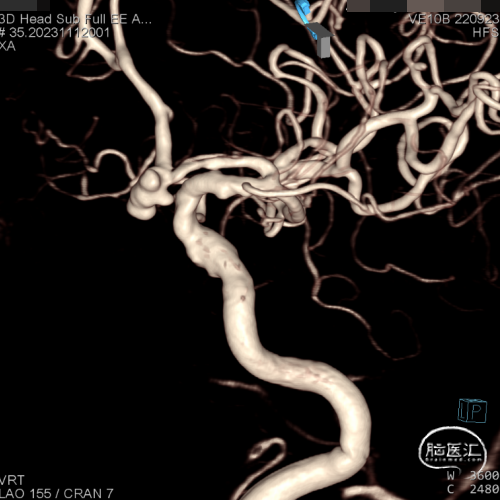

脑血管造影及3D重建示前交通动脉瘤,大小约7.6*5.2*4.8mm,瘤颈宽3.8mm,3个子瘤分别朝向不同方向,瘤颈处子瘤朝向对侧上方,考虑为动脉瘤破裂处。